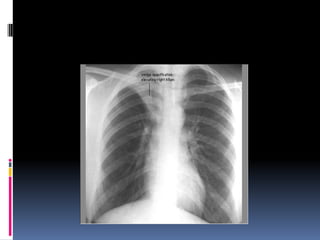

Penetration / Exposure Able to see ribs through the heart  Barely see the spine through the heart  Pulmonary vessels can be traced nearly to the edges of the lungs

Positioning / Rotation Doesthe thoracic spine align in the center of the sternum and between the clavicles? Clavicles – equidistant from spine

Determine side –? L/R  Gastric bubble should be on the left ( normally )